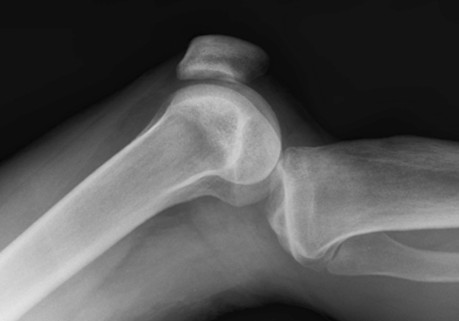

Posterior dislocation

Posterior subluxation